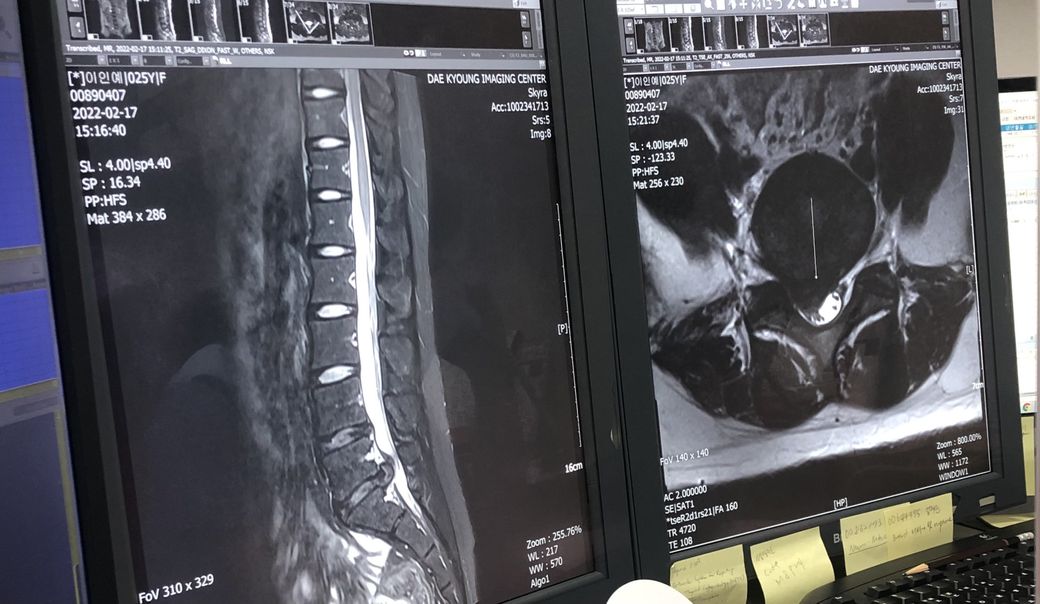

허리디스크 수술 해야할까요?보존치료도가능할까요?

27살 여자구요 주로 앉아서 일하고 고개와 허리를 굽혀 일합니다. 약 한달전부터 허리가아팟고 동네 정형외과애서 엑스레이를찍고 mri권유를 해서 더큰 정형외과로 갔습니다 .그병원에서도 엑스레이를 먼저찍었는데 아직 젊어서 괜찮을거라 하시며 영상판독은 나중에 하자며 약복용과 물리치료(골반견인) 해왔습니다. 그때부터 다리저림(절뚝거림) 과 엉치뼈쪽 고통과 앉을때와 서있을때도 고통이있어 결국 다니던 정형외과와 제휴?를 맺은 곳에서 영상을찍었는데 그 곳 의사분은 시술이나 수술을 고려해봐야할 정도라고 하셨고 영상씨디를 다시가지고와 정형외과에서 꼬리뼈주사(신경차단) 을맞고 수술이나 시술은 보류해보자면서 몇일이지났는데도 통증은 여전해 다시 병원을 갔는데 지금도 약이 쎈거라 하시면서 진통제를 더 처방해주셨는데 고통은 살짝 줄었지만 욱씬하고 얼얼한느낌은 계속납니다. 제가 꼭 수술이나 시술을 해야하는지 궁금하고 제증상이 심한건지 알고싶습니다.

허리 MRI자체만을 보자면 현재 디스크의 탈출 정도는 심한편입니다.

하지만 허리디스크의 수술을 결정함에 있어서 가장중요한 것은 환자분의 증상입니다.

현재 근력의 저하가 없는 상태라면 증상이 약물 및 신경차단술 등으로 호전이 있고참을만 하다면 경과관찰이 가능하지만 이러한 치료에도

효과가 없고 참을수 없는 통증이라면 이는 수술적치료를 통해 디스크를 제거해 주시는 것이 좋을것 같습니다.

• MRI 소견을 통해 보았을 때에 질문자님의 디스크 상태는 매우 심한 편으로 보입니다. 하지만 그와는 별개로 하지의 근력 저하나 감각 저하와 같은 신경학적 소견 없이 통증만 있는 상태라면 시술 보다는 코어 근육 강화, 체중 감소 등을 통해서 척추에 가해지는 부담 자체를 줄여 디스크의 호전을 기대해보시는 것이 근본적인 해결법입니다. 시술을 받으면 당장은 어느 정도 호전될 수 있지만 다시 디스크가 악화될 우려가 높습니다.